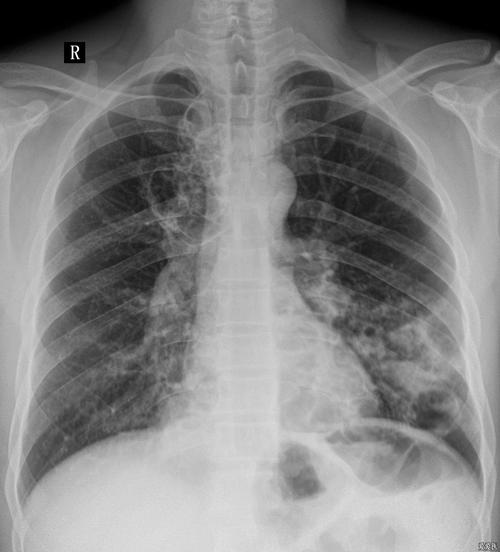

胸部正位dr片双肺多发透亮影